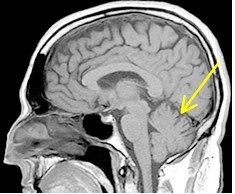

正常の小脳 脊髄小脳変性症